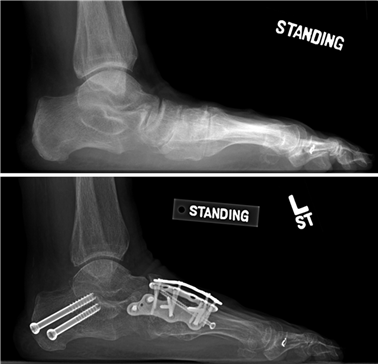

First MTP Arthrodesis

In cases of end-stage hallux rigidus, first MTP arthrodesis yields excellent, predictable outcomes. A dorsal longitudinal incision is made just medial to the EHL tendon. The joint is exposed, and aggressive cheilectomy is performed to remove all dorsal, medial, and lateral osteophytes. The remaining articular cartilage on the metatarsal head and the base of the proximal phalanx is resected using cup-and-cone reamers, which allow for infinite adjustment of the joint position prior to fixation.

Positioning of the fusion is the most critical step of the operation. The hallux must be positioned in 10-15 degrees of valgus, 15-20 degrees of dorsiflexion relative to the first metatarsal, and neutral rotation. Excessive dorsiflexion causes shoe impingement, while insufficient dorsiflexion leads to vaulting during gait and interphalangeal joint arthritis. Fixation is most reliably achieved using a pre-contoured dorsal locking plate combined with a lag screw crossing the fusion interface.

Image

Phase 3: Transition and Strengthening (Weeks 6 - 12)

Upon radiographic confirmation of bridging trabecular bone, patients are weaned from the CAM boot into a stiff-soled athletic shoe with a wide toe box. Physical therapy is formally initiated, focusing on intrinsic foot muscle strengthening, restoration of the windlass mechanism, and proprioceptive training. Aggressive MTP joint mobilization is continued. Patients are counseled that mild to moderate swelling is expected and may persist for up to 6 months post-operatively.

Phase 4: Return to High-Level Activity (Weeks 12+)

By 12 weeks, the osteotomy or fusion site should be solidly united. Patients are cleared for high-impact activities, running, and jumping, provided they have regained adequate strength and have no pain with provocative testing. Shoe wear restrictions are gradually lifted, though patients are continually advised against the chronic use of narrow, high-heeled footwear to prevent late recurrence of angular deformities.